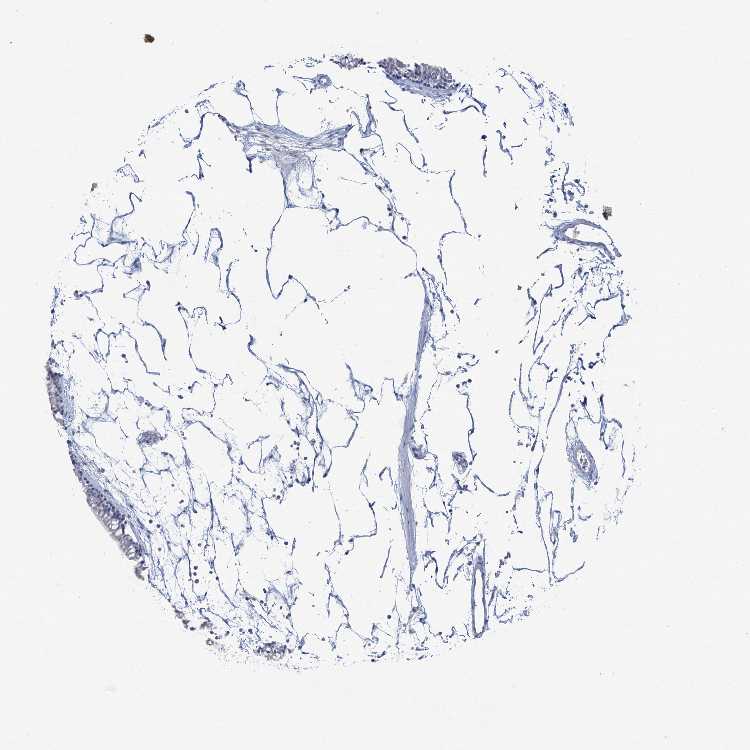

TISSUE PRIMARY DATA NASOPHARYNX Show tissue menu

NASOPHARYNX - Antibody stainingi

Antibody staining in the annotated cell types in the current human tissue is reported as not detected, low, medium, or high, based on conventional immunohistochemistry profiling in selected tissues. This score is based on the combination of the staining intensity and fraction of stained cells.

Each image is clickable and will lead to virtual microscopy that enables deeper exploration of all samples and also displays staining intensity scores, fraction scores and subcellular localization as well as patient and tissue information for each sample.

Antibody HPA017369Antibody CAB000023Antibody CAB040544Antibody CAB055506Antibody CAB058688

Respiratory epithelial cells Not detectedNot detectedNot detectedNot detectedNot detected